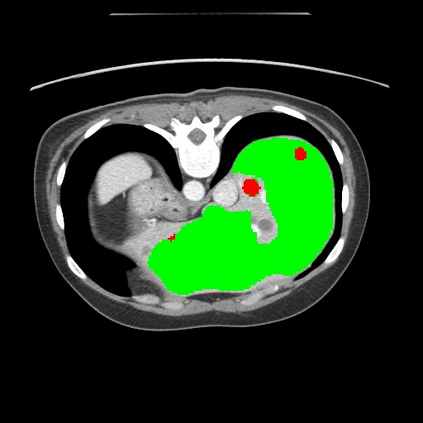

Transformers have made remarkable progress towards modeling long-range dependencies within the medical image analysis domain. However, current transformer-based models suffer from several disadvantages: (1) existing methods fail to capture the important features of the images due to the naive tokenization scheme; (2) the models suffer from information loss because they only consider single-scale feature representations; and (3) the segmentation label maps generated by the models are not accurate enough without considering rich semantic contexts and anatomical textures. In this work, we present CASTformer, a novel type of generative adversarial transformers, for 2D medical image segmentation. First, we take advantage of the pyramid structure to construct multi-scale representations and handle multi-scale variations. We then design a novel class-aware transformer module to better learn the discriminative regions of objects with semantic structures. Lastly, we utilize an adversarial training strategy that boosts segmentation accuracy and correspondingly allows a transformer-based discriminator to capture high-level semantically correlated contents and low-level anatomical features. Our experiments demonstrate that CASTformer dramatically outperforms previous state-of-the-art transformer-based approaches on three benchmarks, obtaining 2.54%-5.88% absolute improvements in Dice over previous models. Further qualitative experiments provide a more detailed picture of the model's inner workings, shed light on the challenges in improved transparency, and demonstrate that transfer learning can greatly improve performance and reduce the size of medical image datasets in training, making CASTformer a strong starting point for downstream medical image analysis tasks.